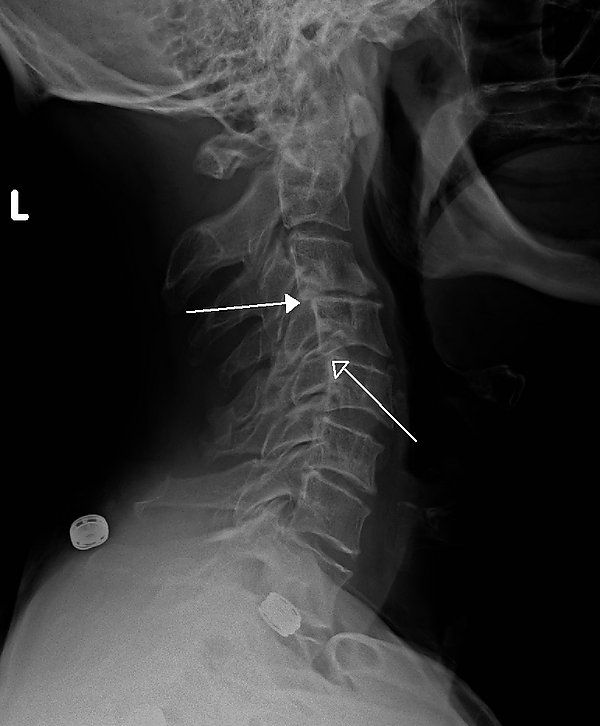

Ретролистез

Ретролистез — смещение позвонка назад. Чаще всего встречается в шейных позвонках или в пояснице, немного реже — в позвонках грудной области.

• ступенчатый: тело одного позвонка смещено назад по отношению к вышележащему позвонку и вперед от нижележащего позвонка;